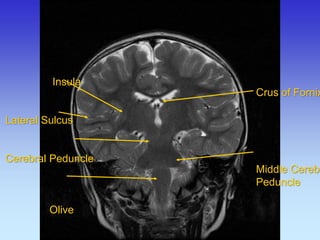

Insula Lateral Sulcus Cerebral Peduncle Olive

Crus of Fornix

Middle Cerebellar

Peduncle